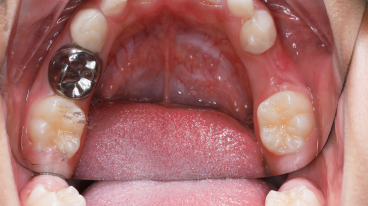

SSC (Stainless Steel Crown) là mão răng bằng thép không gỉ, được thiết kế sẵn với nhiều kích cỡ khác nhau, thường dùng để phục hồi răng sữa đã bị sâu lớn hoặc tổn thương nặng. Đây là một dạng phục hình toàn phần bao phủ toàn bộ thân răng, giúp bảo tồn và duy trì chức năng của răng sữa cho đến khi thay răng vĩnh viễn.

Mão SSC giúp bao phủ toàn bộ thân răng, giảm nguy cơ nứt vỡ và tái nhiễm khuẩn.

- Tỉ lệ thành công cao